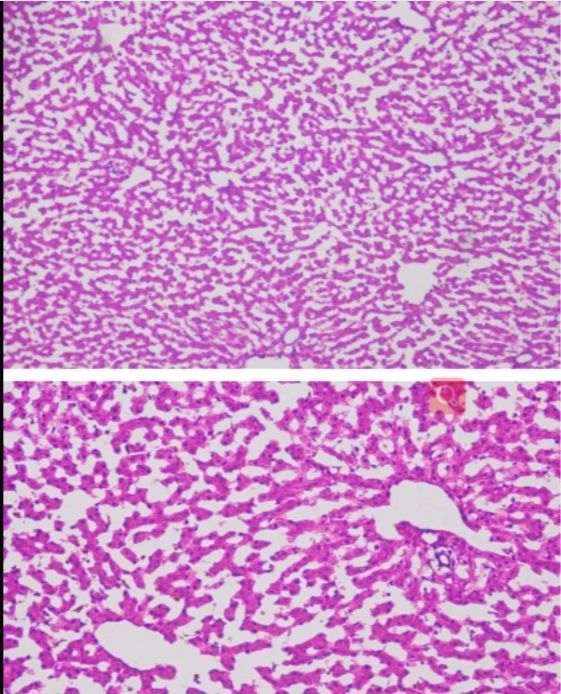

小鼠大腦冰凍切片

→其次,通過(guò)顯微鏡觀察切片的染色情況和清晰度,優(yōu)質(zhì)的切片應(yīng)展現(xiàn)出清晰的細(xì)胞和組織結(jié)構(gòu)。

→根據(jù)顯微鏡下的觀察,鑒別切片中的組織類型和細(xì)胞形態(tài)。不同的組織類型和細(xì)胞形態(tài)反映了不同的生理或病理狀態(tài)。

→注意觀察細(xì)胞的大小、形狀、排列方式以及細(xì)胞核和細(xì)胞質(zhì)的特征,這些特征可以提供關(guān)于細(xì)胞狀態(tài)的重要線索。